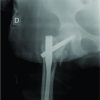

A 46-year male after a motorbike accident sustained right heel pad avulsion with no associated bony injury. The patient’s other injuries were assessed after resuscitating and stabilizing him first. Physical examination of the wound was done to know the severity of soft-tissue injury, the sensation of the flap, wound contamination, neurovascular damage, and associated bony injury. Examination showed a viable heel pad flap, the wound was contaminated (Fig. 1). An initial dosage of broad-spectrum antibiotics was administered intravenously. A radiograph of the foot and ankle was obtained to identify the associated skeletal injury. The severity of the trauma and its complications was explained to the patient and his relatives along with the operative procedure and its complications. Surgery was performed within the golden period of 6 h. Under regional anesthesia, debridement and wound lavage were given with 10L normal saline. The heel pad was anchored to the calcaneus with the help of multiple 1.8 mm Kirschner wires with a gap of approximately 2–3 cm between each k wire (Fig. 2).

Wound edges were refreshed and kept open to prevent wound tension. Wound dressing and plaster splinting were done. Three doses of post-operative intravenous antibiotics were given. Check dressing done on the 2nd post-operative day to check the viability of heel pad and infection. The patient was discharged on the 3rd post-operative day with oral antibiotics. Follow-up was advised every 3rd day for 2 weeks for wound dressing. Toe-touch weight-bearing was encouraged after 2nd week. Wound flap healing was assessed weekly. Kirschner wires were removed after 4 weeks and partial weight-bearing was encouraged (Fig. 3). Full weight-bearing was advised at the 12th week (Fig. 4). A 1-year follow-up was advised for the patient.